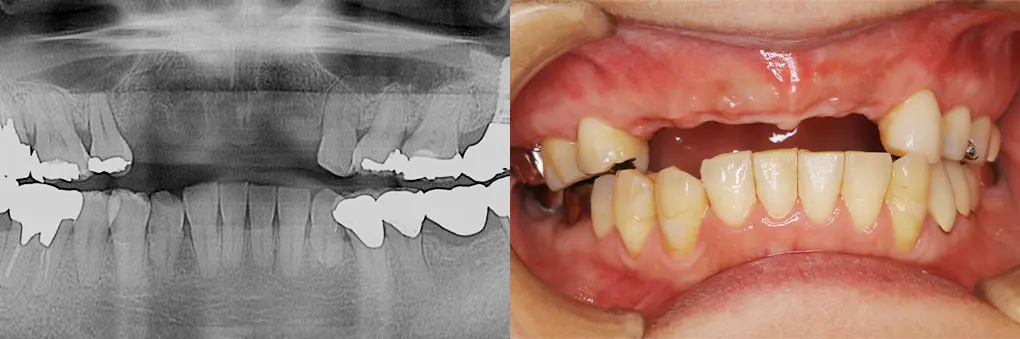

【症例4】入れ歯をインプラントで固定式ブリッジに(40代女性)

| 主訴・背景 | 取り外し式の入れ歯をインプラントで治療したい |

|---|---|

| 診断・治療前の状態 | 抜歯後2カ月のため抜歯窩が存在 矯正治療後前歯部歯根が吸収して、歯の動揺がひどくなり可徹式義歯を装着 |

| 治療方針・計画 | インプラント埋入と同時に骨造成術を併用 |

| 手術・処置内容 | ⚫︎ 治療部位13,11,22 インプラント3本 ⚫︎ 骨造成術を併用治療 ⚫︎ ストローマン社 BL BLT ⚫︎ 上部構造 ジルコニアセラミックブリッジ |

| 治療期間・回数 | 仮歯装着まで2カ月、最終補綴装着まで2カ月、トータル4カ月/6回 |

| 費用・料金(自費診療の場合) | 1,800,000円 |

| リスク・注意点・術後ケア | セラミックの破折、インプラント周囲炎、定期検診 |

| 治療後の状態・経過写真 | 「違和感なく以前の自身の歯よりきれいになりました」 現在、7年経過良好。遠方からの来院のため6カ月定期検診 |

| まとめ・院からのコメント | 学生時代に矯正治療を受け20年後歯の動揺が出現し、近医で抜歯、可徹式義歯装着と失望感が強かった患者様が笑顔になり嬉しく思います。 |